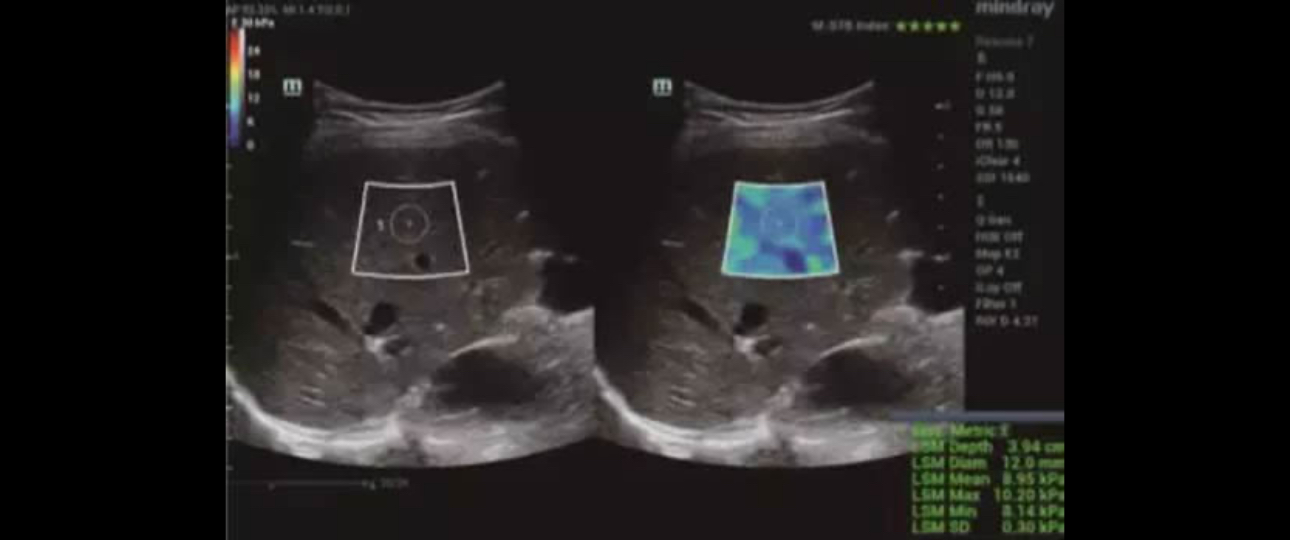

Applying with the Sound Touch Elastography, the system showed a median value of 8.83 kPa (IQR/M = 1.8%) which indicated significant fibrosis. The liver stiffness measurement was also reliable.

STE image shows a median value of 8.83 kPa

With availability of an ultrasound system, in which shear wave elastography technique is implemented, experts were able to evaluate the liver stiffness whose results were compatible with significant fibrosis (F2), confirmed by liver biopsy later.